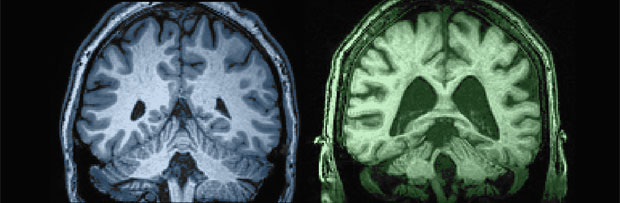

Cervello a 27 anni (sinistra) e a 87 anni.